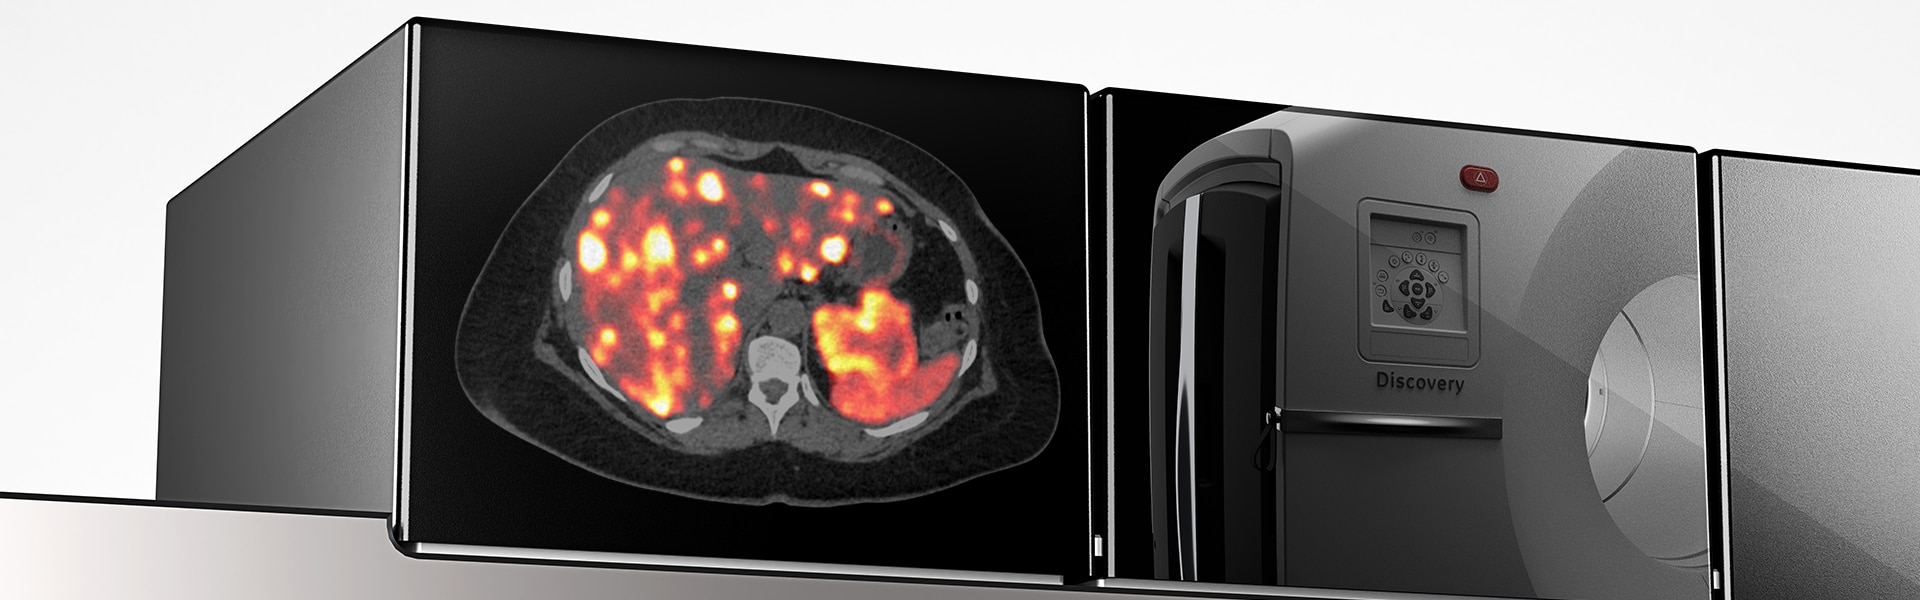

Images cliniques

Lésions multiples au niveau des jambes et du cou

Petite lésion de l'oreille et tumeur de la hanche.

Lésion cervicale à droite mesurant 6 mm.

Acnée visible sur le dos

Poumon droit, aine droite et tumeur derrière le genou droit.

Cancer de la tête et du cou.

Évolution du cancer après la radiothérapie. Minuscule cancer du sein.

Ganglions lymphatiques avec fixation de FDG au niveau de l’aisselle gauche (vaccination contre la COVID-19).